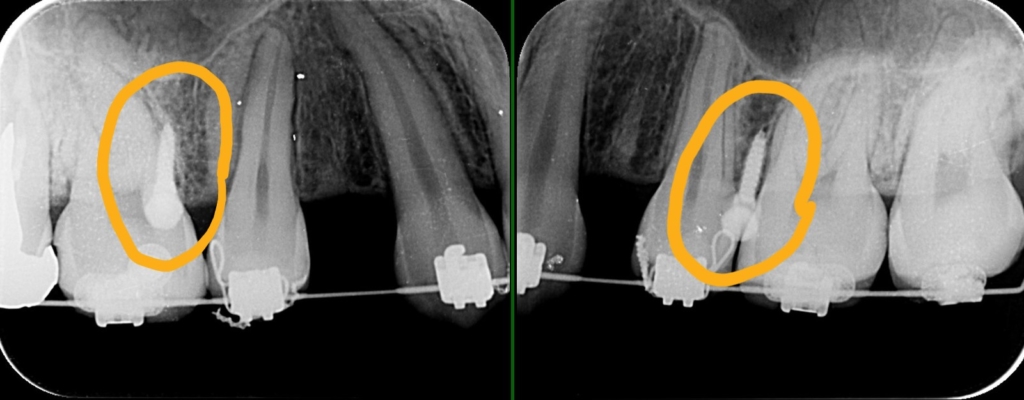

上の歯列を更に後方へ移動させるためには、右上の埋伏した智歯が邪魔でした。

しかし、その歯は神経を取り、内部を大きく削り残った歯質が薄くなり弱くなっています。

さらに言うと神経を取る治療にステップで治療器具を折れ込ませてしまったようです。

普通なら埋伏している智歯を抜歯するのですが、今回、手前の奥歯の条件が悪かったので、あえて手前の差し歯になっている奥歯(赤い線で囲われた歯)を抜歯して、埋っている智歯(青い線で囲われた歯)を残して、将来萌出してきて咬合に参加する未来を期待することになりました。